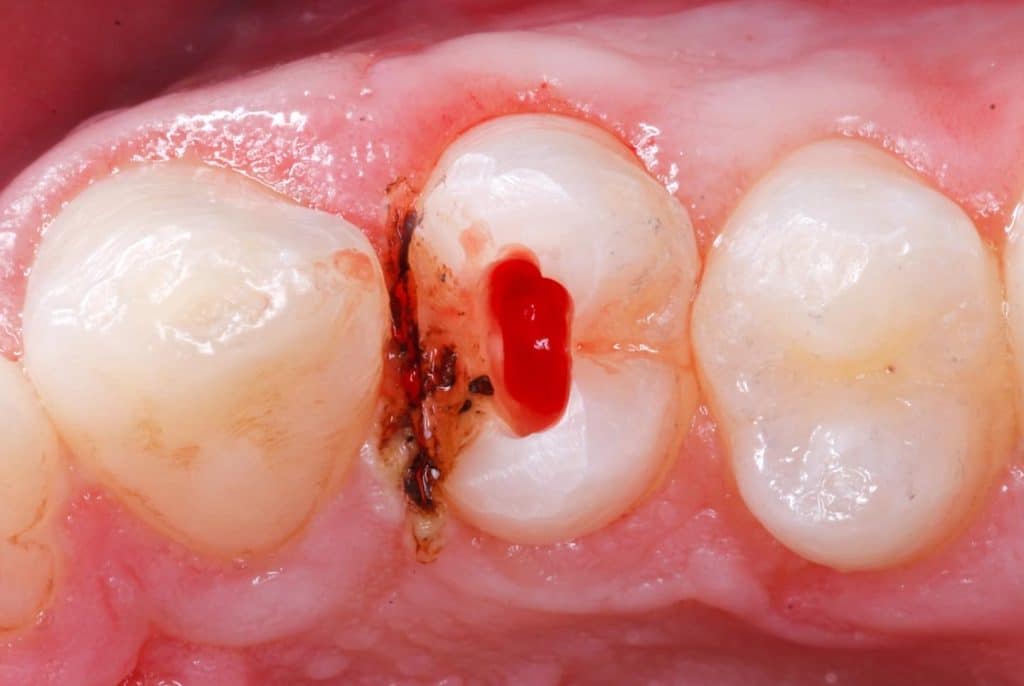

Margin elevation

in this case I’m used a diamond wedge as a matrix to elevate the margin after I finished the margin and replaced the rubber dam after that sandblasting the cavity and repeat the adhesive protocol snd restoring the tooth with bioclear method